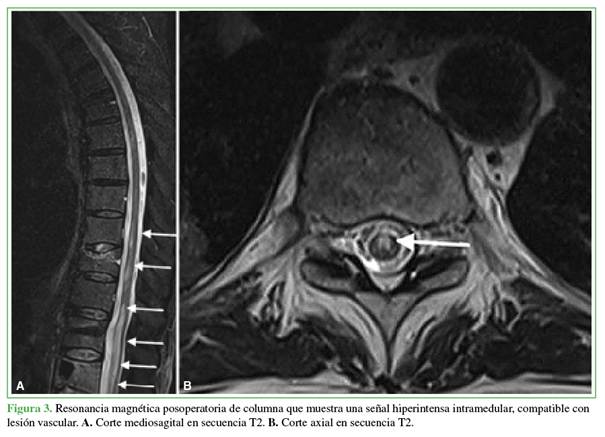

A las 48 h de la cirugía inicial, una resonancia magnética de columna, de urgencia, reveló hiperintensidad intramedular no compresiva compatible con isquemia medular extensa desde T9 hasta L4 (Figura 3). Se la consideró una lesión medular de manejo no quirúrgico; por lo tanto, se reinició el esquema de anticoagulación y se derivó al paciente a un centro de rehabilitación intensiva.